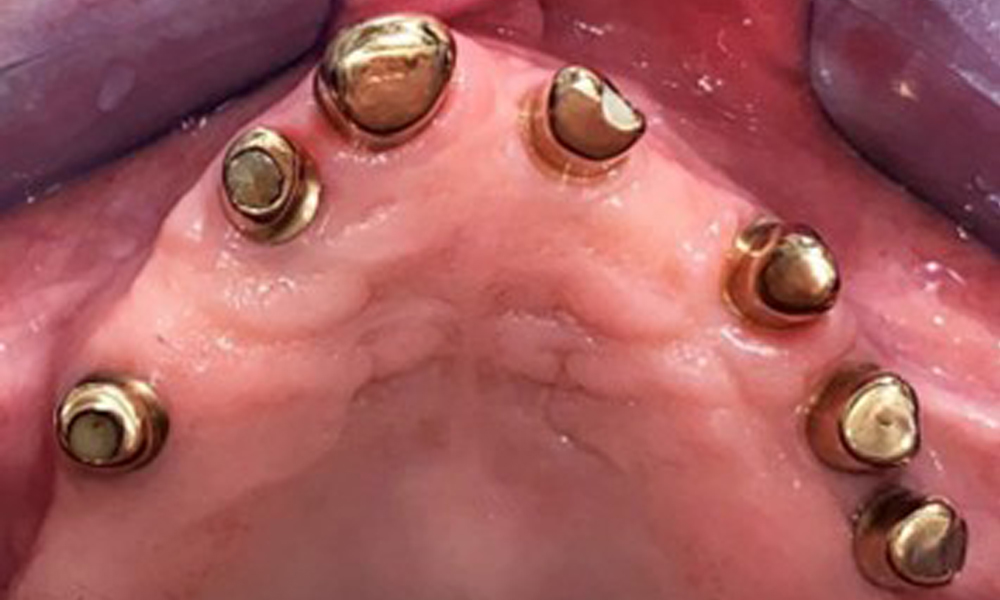

The patient was fitted with a combined removable maxillary telescopic prosthesis more than 25 years ago (Fig. 1, Fig. 2, Fig. 3) and is very happy with her dentures. The patient has an adequate fixed denture for the mandible (Fig. 4).

The dental findings are as follows: Combined removable implant and tooth-supported telescopic prostheses on implants 15, 13, 21, 23, 24, 25 and tooth 11 (Fig. 1, Fig. 2, Fig. 3). The patient was fitted with a fixed mandibular denture. Adequate bridges were present over 37 to 34 and 45 to 47 (Fig. 4), the crown margins were intact and there were no active caries. A composite filling with a marginal gap was present on tooth 43. There was mandibular gingival recession, exposing 1 to 3 mm of root surface. This also applies to 11.

The periodontal status should be thoroughly examined once a year. This examination provides comprehensive documentation of the periodontal and implant findings, including pocket depths, periodontal recession and furcation involvement. This will ensure a rapid response to any potential progression of the mucositis, gingivitis, periodontitis or peri-implantitis. Implant probing using a plastic probe is recommended. In the present case, a mesial probing depth of 4 mm was detected mesial to implant 23. No suppuration or bleeding was detected, indicating the absence of peri-implantitis.